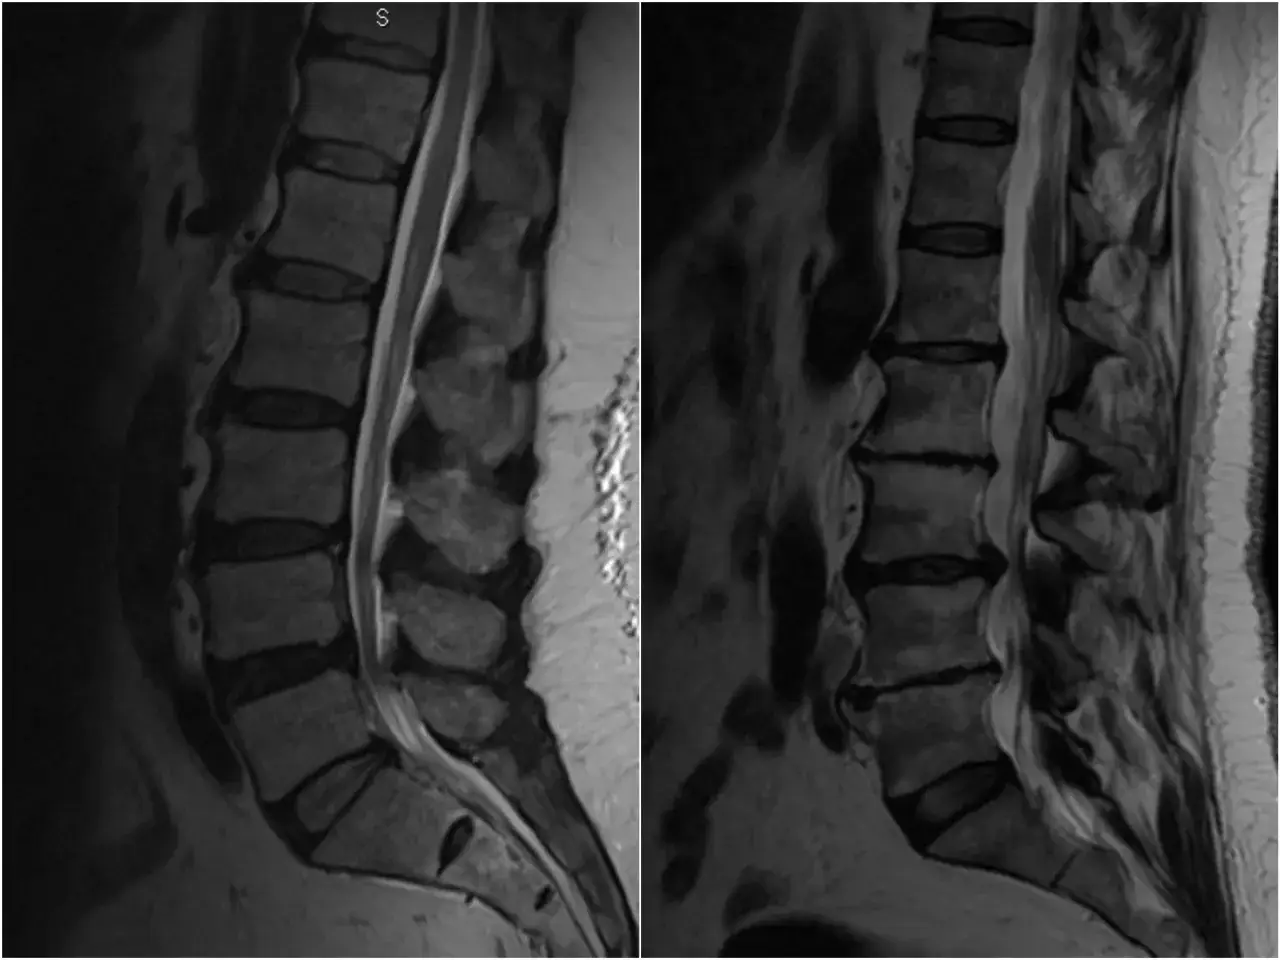

Rezonans magnetyczny (MRI): Złoty standard w obrazowaniu przyczyn ucisku

Najdokładniejszą metodą obrazowania struktur kręgosłupa i nerwów jest rezonans magnetyczny (MRI). Badanie to pozwala na precyzyjne zobrazowanie krążków międzykręgowych, rdzenia kręgowego, korzeni nerwowych oraz ewentualnych zmian patologicznych, takich jak przepukliny dysków, stenoza czy guzy. MRI jest uważane za "złoty standard" w diagnostyce przyczyn ucisku na nerwy w odcinku lędźwiowym, ponieważ dostarcza szczegółowych informacji niezbędnych do zaplanowania skutecznego leczenia.